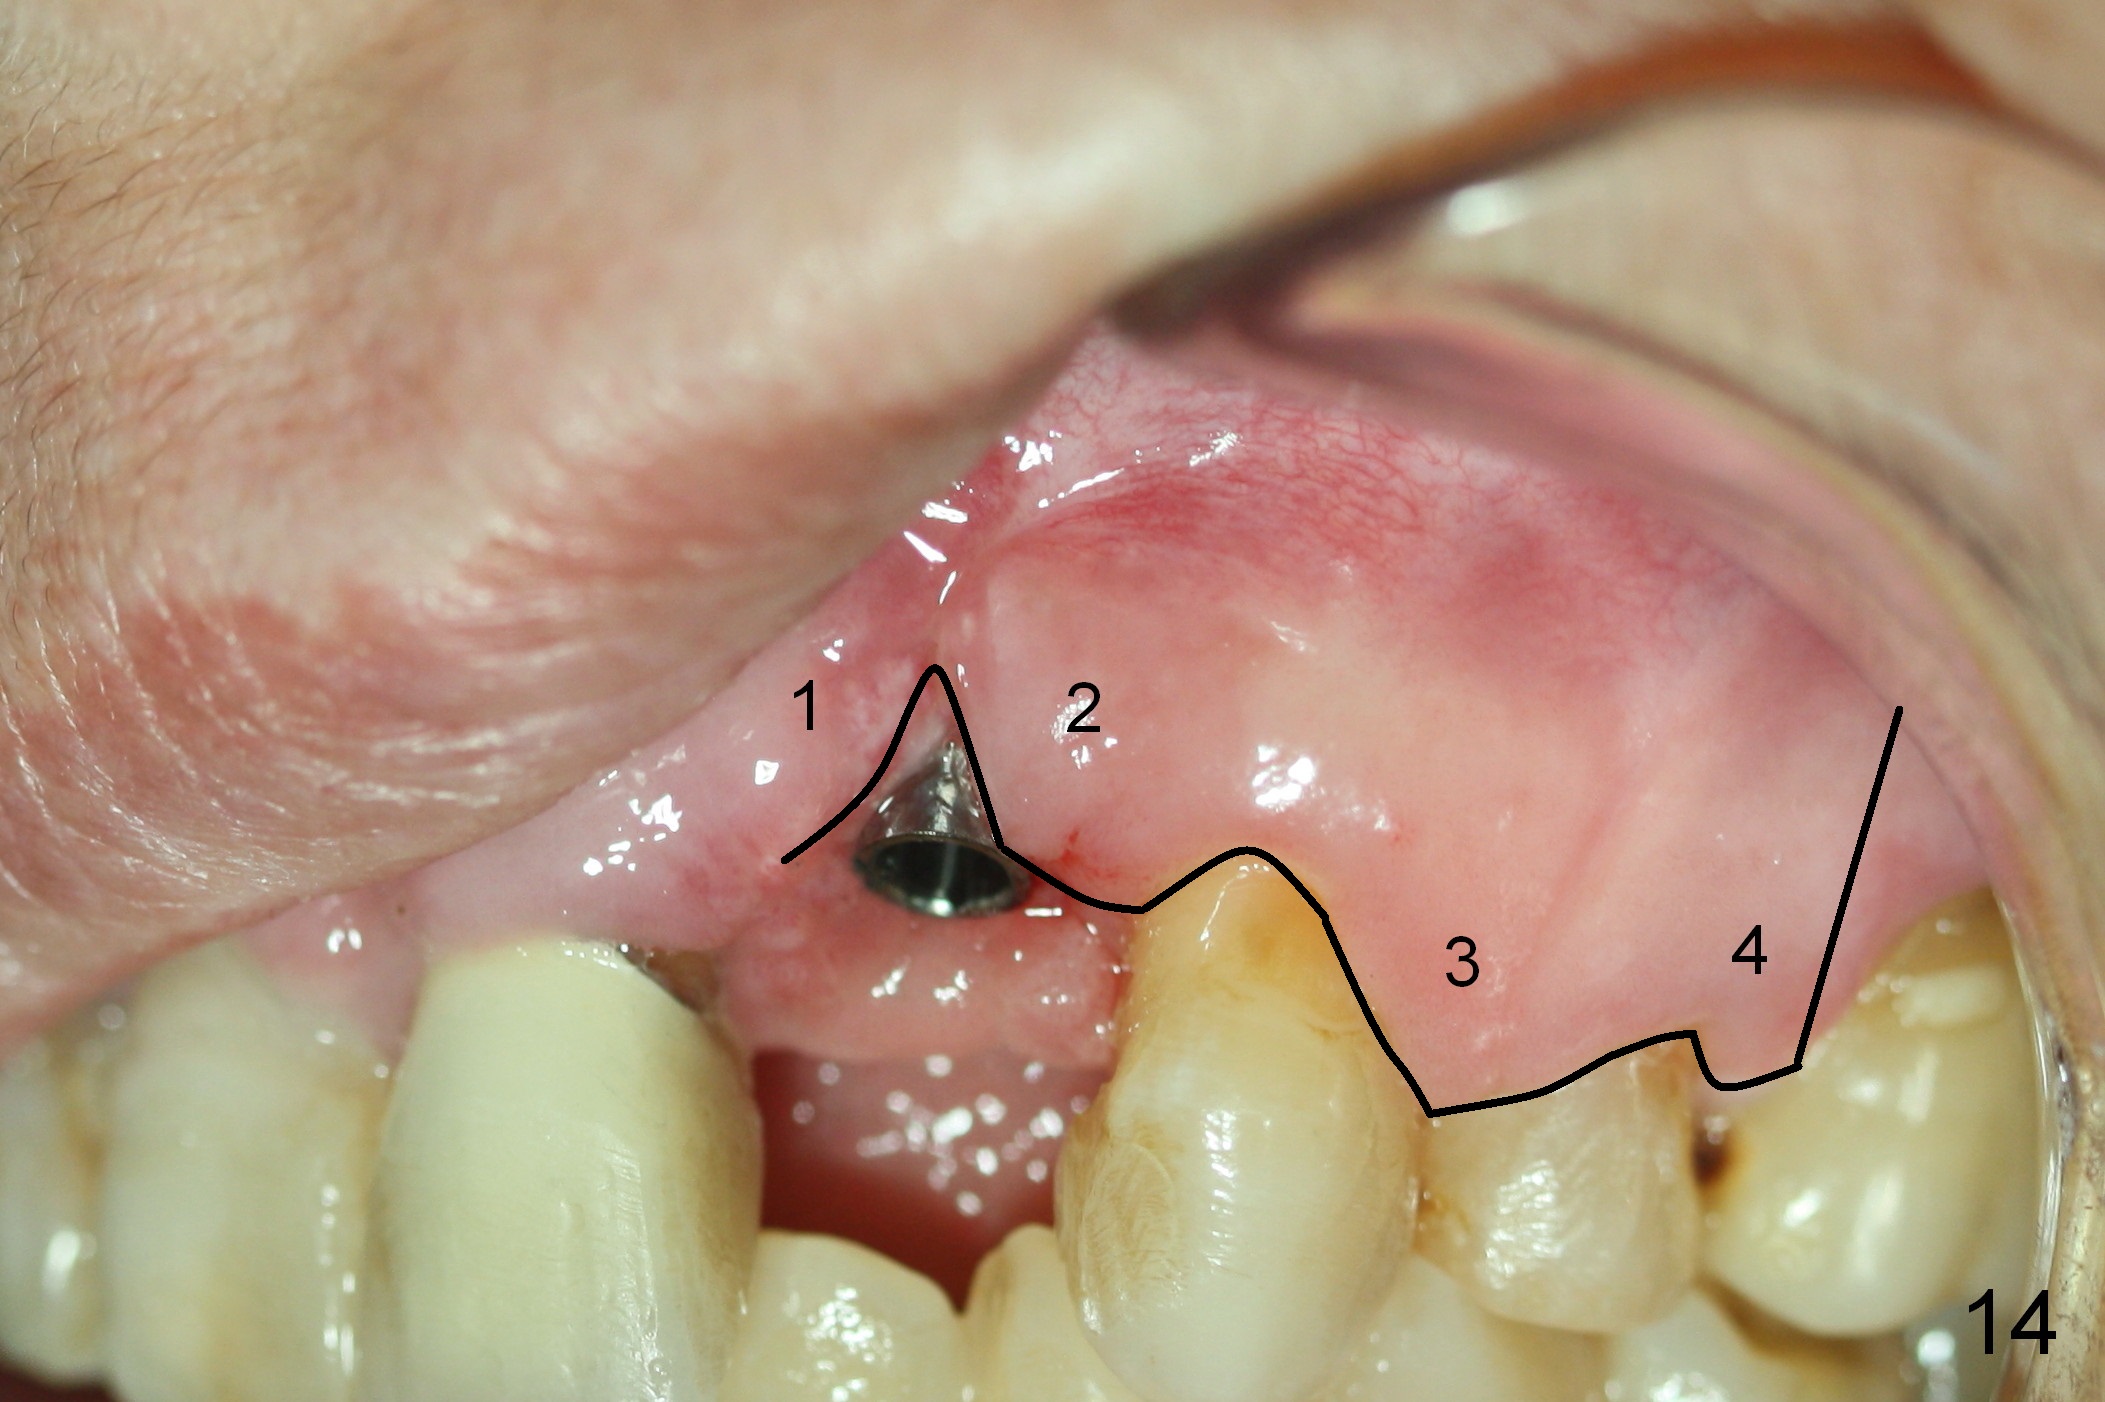

As expected, there is midbuccal tissue deficiency (Fig.9,10: 2 months postop). After discussion, a free gingival graft from the palate is placed (Fig.11,12 *). Two weeks later, the graft sloughs (Fig.13). A pedicled flap is designed (Fig.14) and transferred to repair the defect (Fig.15,16).